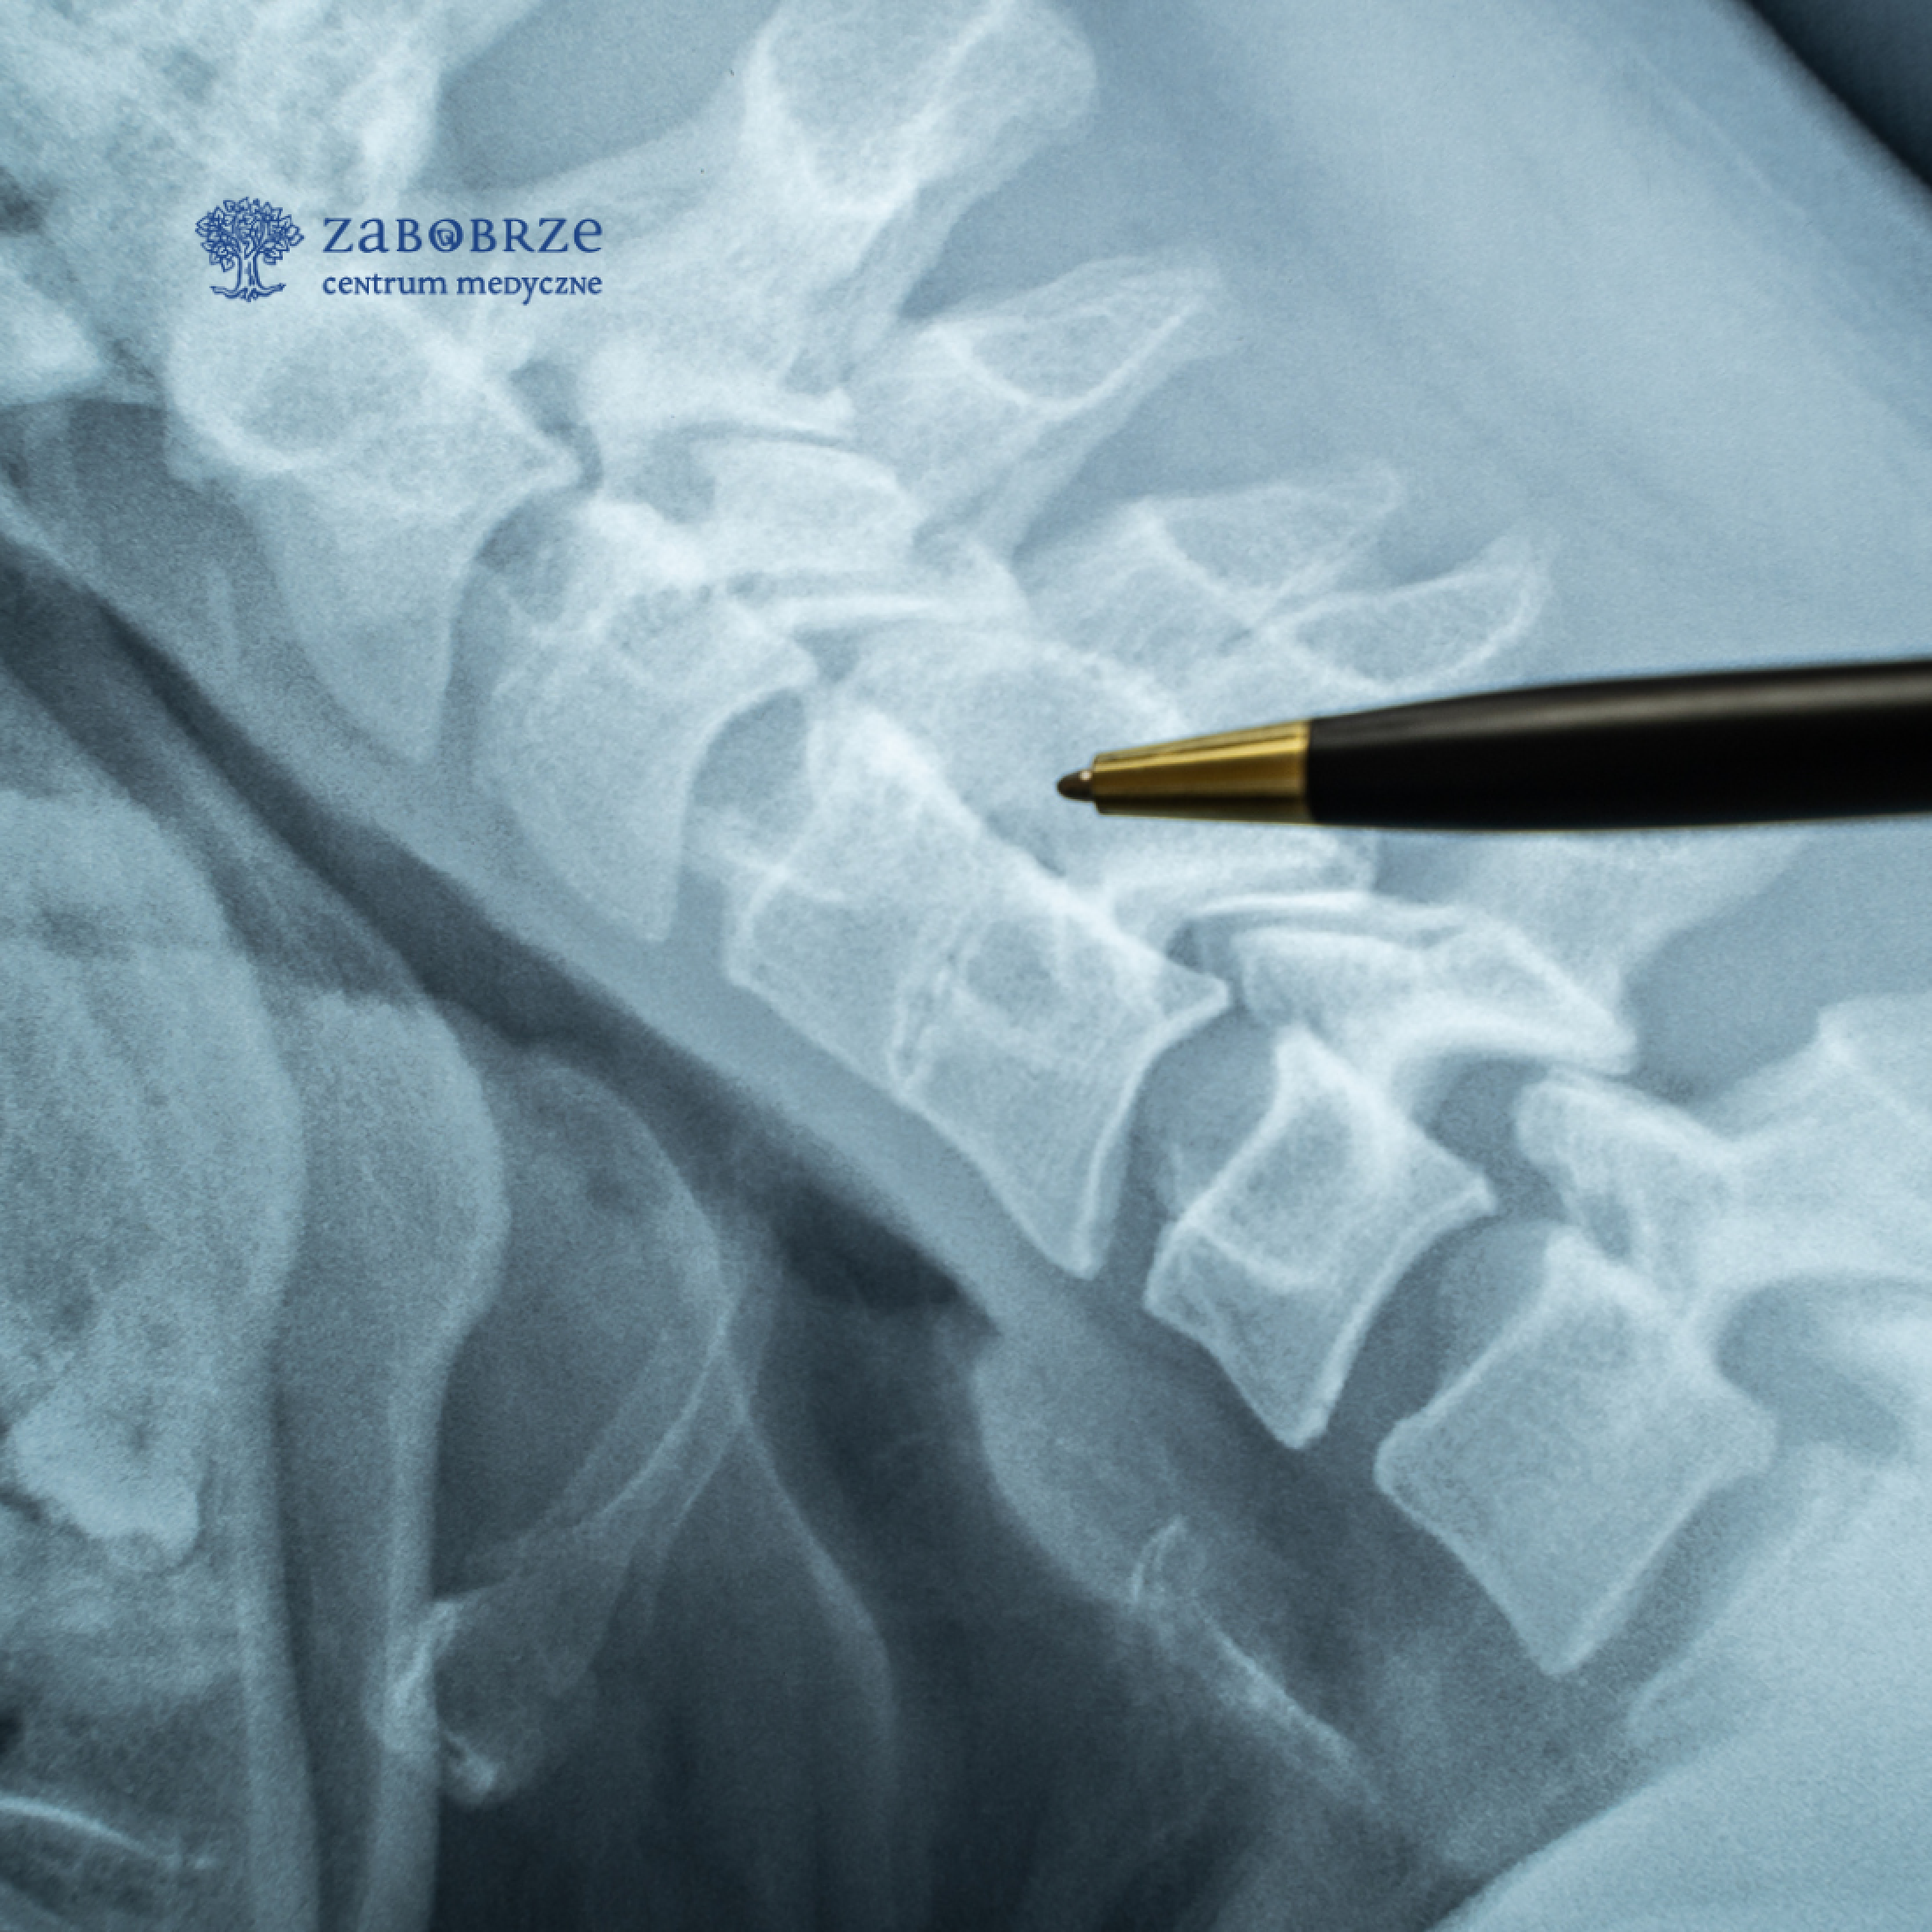

Z radością informujemy, że do zespołu Centrum Medycznego Zabobrze dołączył wybitny specjalista w dziedzinie neurochirurgii – lek. med. Paweł Antczak. To ekspert, który wnosi do naszej placówki nowoczesne podejście do leczenia zespołów bólowych kręgosłupa, ze szczególnym uwzględnieniem małoinwazyjnych i endoskopowych technik operacyjnych.

Dr Paweł Antczak zdobywał swoje doświadczenie zawodowe w renomowanych klinikach neurochirurgii w Polsce i Niemczech. Jego specjalizacja obejmuje leczenie zespołów bólowych kręgosłupa i operacje, które minimalizują ryzyko powikłań oraz znacząco skracają czas rekonwalescencji pacjentów. W swojej pracy dr Antczak skupia się na indywidualnym podejściu do pacjentów, oferując skuteczne metody leczenia.

• Blokady przeciwbólowe pod kontrolą USG i RTG, w tym zastrzyki około- i przykręgosłupowe oraz blokady nadtwardówkowe, które skutecznie łagodzą ból kręgosłupa.

• Termolezja – nowoczesna procedura zwalczania bólu spowodowanego zmianami zwyrodnieniowymi kręgosłupa. Dzięki tej technice pacjenci mogą wrócić do codziennych aktywności bez bólu i z większym komfortem.

Dołączenie dr Pawła Antczaka do zespołu Centrum Medycznego Zabobrze to kolejny krok w kierunku oferowania mieszkańcom Jeleniej Góry i okolic opieki medycznej na światowym poziomie. Zapraszamy do umawiania wizyt i konsultacji z naszym nowym specjalistą, który pomoże Państwu w walce z bólem kręgosłupa oraz innymi dolegliwościami wymagającymi konsultacji neurochirurgicznej - telefon +48758890170 wew. 2.